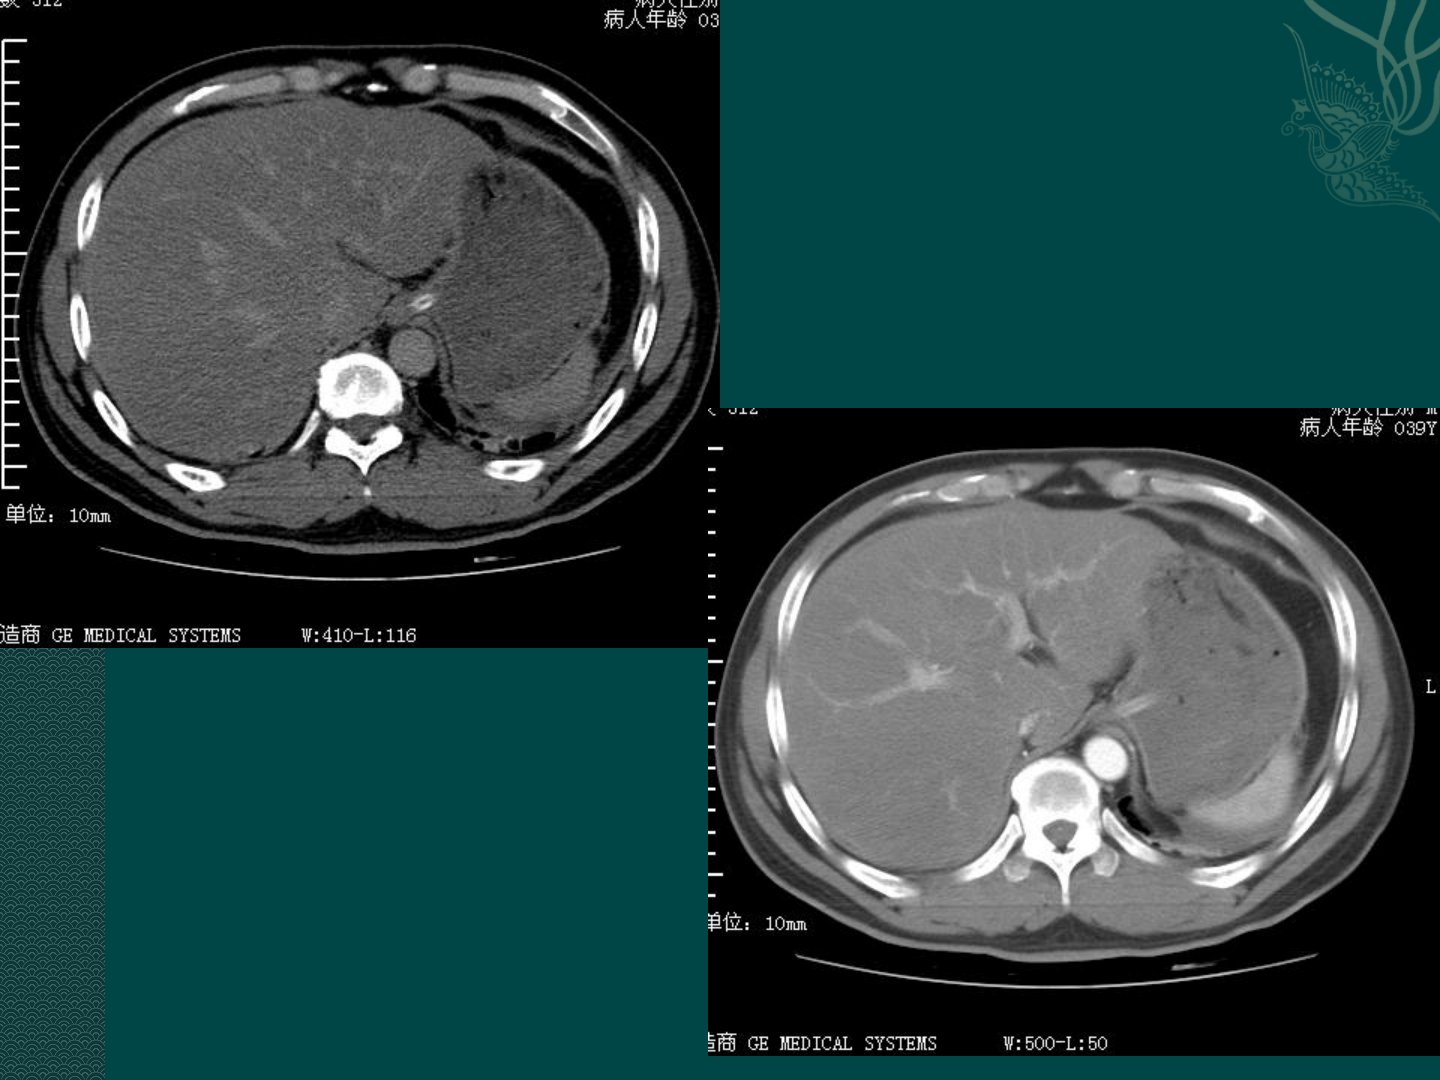

患者39岁男性有长期饮酒史体检发现肝功异常。查体显示腹软肝肋下5CM质软无压痛。临床印象诊断考虑为酒精性脂肪肝。可选影像检查方法包括腹部B超、CT、MRI其中首选腹部B超。影像学表现方面腹部平扫显示肝包膜紧绷圆钝全肝脏密度降低且较脾脏低肝内血管呈相对高密度影;增强CT则显示肝脏强化较脾脏差肝内血管显现更清晰。影像学诊断为弥漫性脂肪肝。诊断主要依据包括患者长期饮酒史、查体结果及影像学表现。此病变需与肝硬化鉴别肝硬化CT表现为肝轮廓凹凸不平、肝门干裂增宽且CTA可显示门脉高压继发的侧支循环增粗扭曲。